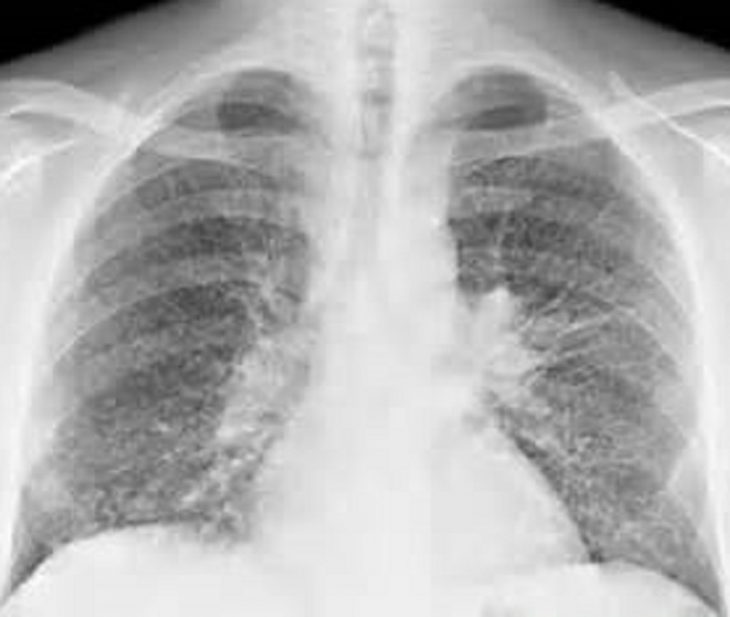

метастазы в легких при рентгене